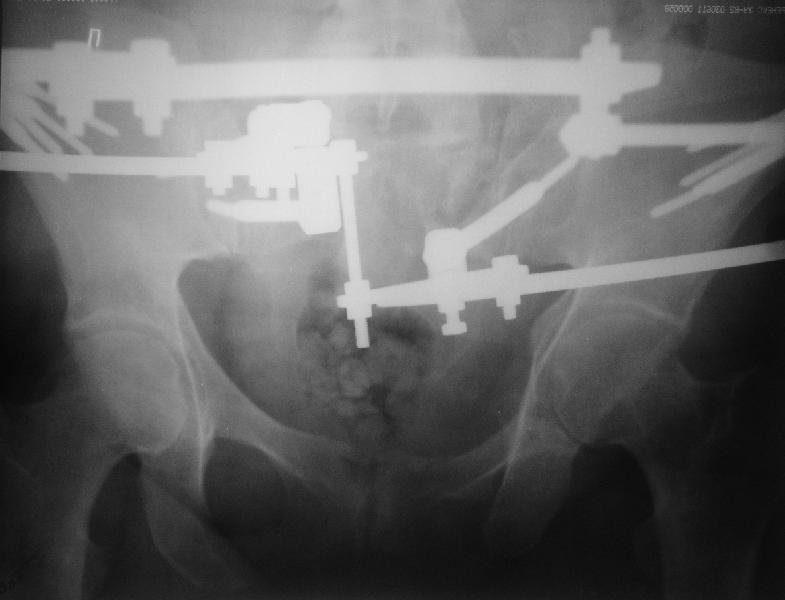

Мне нравится ваша закрытая репозиция девятимесячного ложного сустава, не знаю насчет туннелизации, но шурупы в 7.2 это серёзная конструкция. При стабильной фиксации крестец должен срастись, только я бы держал передний фиксатор до шести недель, костыли, а полную нагрузку разрешить через 12 недель.

При желании, передную фиксацию можно было перевести в малую нижнюю (супрацетабулярно хорошая костная масса), стержни провести через spina ilica anterior inferior в место прикрипления прямой мышцы бедра.

Нижний фиксатор немного миниатюрнее и удобнее для больной.

Примерно такой фиксатор наложил вчера ночью, но патология была экстренная травма: больному 53 года, поступил после мотоциклетной травмы, черепно-мозговой, абдоминальной, челюстно лицевой с потерей одного глаза, сосудистой и из скелета перелом крестца слева с диастазом симфиза и множественные переломы ребер.

Одновременно с хирургами, которые занялись ксплоративной лапаротомией, мы приступили к фиксации временным аппаратом для уменьшения диастаза симфиза. После установки аппарата удалось стабилизировать давление, потом наше место занял сосудистый хирург, который нашел кровоточащую левую артерию epigastrica. Кровоточаший сосуд затромбизировал эндоваскулярно введением 4 coil placement.

Много кровепотери было из лицевых ран. Кроме забрюшинной гематомы, крови накопилось в абдоминальной части между мышечными стенками и под кожей. Кровопотерю заместили более 20 доз препаратов крови и INR опустился изначалнего 9.5 до 1.0 в конце. Находится в реанимации, стабильный, надеемся через несколько дней займемся окончательной фиксацией переломов костей таза.